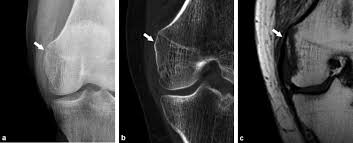

Pain and restriction of movements. The cause of the knee effusion is unknown. It is likely that this patient has been an active sportsman in the past. #foamed #foamrad #radiology #rad #elearnrad #voxelz #varunbabu #drbabu. Pellegrini stieda syndrome is a medical problem which is characterized by pain, swelling and inflammation in the knee. Most of the cases of pellegrini stieda lesions are not symptomatic, and pellegrini stieda syndrome is said to exist when the lesion becomes symptomatic i.e. Ayurvedic treatment is the natural way to treat pellegrini stieda syndrome. Is the presence of a radiological finding of calcification on the medial side of the knee as a consequence. The diagnosis pellegrini stieda disease was made. It is a common incidental finding on knee radiographs. With the ayurvedic treatment, it is possible to avoid surgery. This occurs due to the deposition of calcium on the inner side of the knee. Learn about this soft tissue calcification around the knee joint.

Pellegrini stieda syndrome is a medical problem which is characterized by pain, swelling and inflammation in the knee. The diagnosis pellegrini stieda disease was made. Learn about this soft tissue calcification around the knee joint. The cause of the knee effusion is unknown. There is a moderately large knee effusion. Pain and restriction of movements. Is the presence of a radiological finding of calcification on the medial side of the knee as a consequence. It is a common incidental finding on knee radiographs. Most of the cases of pellegrini stieda lesions are not symptomatic, and pellegrini stieda syndrome is said to exist when the lesion becomes symptomatic i.e. #foamed #foamrad #radiology #rad #elearnrad #voxelz #varunbabu #drbabu. It is likely that this patient has been an active sportsman in the past. There is evidence of osteoarthritis. This occurs due to the deposition of calcium on the inner side of the knee.